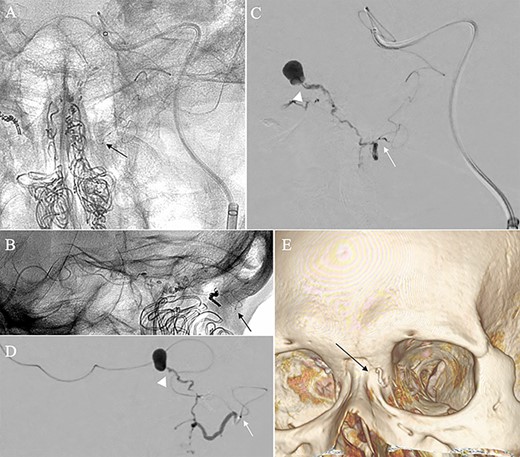

A patient in their 70s with extracranial lymphoma was incidentally found to have ACF–dAVF via head computed tomography and magnetic resonance angiography. Digital subtraction angiography (DSA) confirmed ACF–dAVF with multiple feeding branches, arising from bilateral OphAs, distal IMAs and the left middle meningeal artery (MMA), with cortical venous reflex (Borden type III, Cognard type IV) (Fig. 1). At the patient’s request, we chose endovascular, rather than surgical, treatment. We injected a 20% N-butyl-2-cyanoacrylate (NBCA)–lipiodol mixture into the fistula through bilateral ethmoidal arteries and the left MMA after we placed coils at the terminal branch of the right OphA. However, we could not achieve full penetration into the fistulous connections because of pressure secondary to high flow from the IMA branches, which resulted in incomplete obliteration (Fig. 1). Four months later, we repeated TAE by temporarily reducing nasal blood flow by inserting gauze infiltrated with xylocaine and epinephrine into the nasal cavities. After introducing the guiding catheter, an endonasal surgeon inserted X-ray-detectable surgical gauze infiltrated with 1% xylocaine and epinephrine (1:10 000) into bilateral nasal cavities using a nasal speculum, while paying full attention to avoid damage to the nasal mucosa. Then, we confirmed that the gauzes were placed in appropriate locations in the upper nasal cavity under fluoroscopic guidance. Immediately after insertion, we were able to confirm decreased blood flow from the IMA using DSA (Fig. 2). After this procedure, we navigated a DeFrictor Nano Catheter (Medico’s Hirata, Osaka, Japan) into the terminal branch of the OphA, which was connected to the dorsal nasal artery. Even though there was still a distance from the tip of the microcatheter to the shunt pouch, the NBCA reached the shunt point and penetrated the venous portion (Fig. 3). Follow-up DSA demonstrated complete obliteration of the ACF–dAVF, and blood flow in the nasal mucosa from the IMA branches recovered normally (Fig. 4).

(A) Inserting gauze infiltrated with epinephrine into bilateral nasal cavities. (B and C) Radiograph showing the gauze inserted toward the upper nasal cavity. (D) DSA before inserting the gauze, anteroposterior view, showing blood flow from the right distal IMA. (E) DSA immediately after inserting the surgical gauze, anteroposterior view, showing decreased blood flow from the IMA. (F) Schematic drawing of remaining (red solid line) and occluded feeding arteries (black dotted line) after inserting the surgical gauze. Schema describing that the left dorsal nasal artery (asterisk) remained patent after embolizing the left middle meningeal artery (1), bilateral ethmoid arteries (2) and the right dorsal nasal artery (3), and blood flow from bilateral distal IMAs (4) decreased using our transnasal flow reduction method. (5) Angular artery.